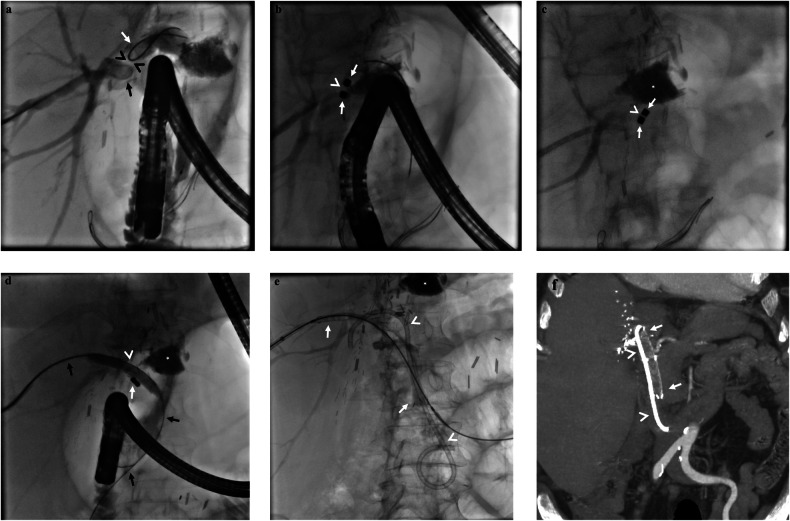

Objectives: To investigate long-term outcomes of combined endoscopic-percutaneous methods for endoscopically unmanageable anastomotic biliary strictures in living donor liver recipients.

Materials and methods: This retrospective single-center study included 144 patients referred for biliary stricture between November 2017 and May 2023. Eighty-eight patients (leak = 8, non-anastomotic stricture = 3, treatment refused = 12, successful ERCP = 65) were excluded. Patients initially underwent percutaneous biliary drainage. Patients for whom percutaneous intervention was successful in traversing stricture were followed up with fully-covered self-expandable metallic stents and/or plastic catheter stents. However, in case of failure, magnetic compression anastomosis (MCA) was performed.

Results: A total of 56 patients (mean age, 59 years ±11; 35 men) comprised the study group. Percutaneous intervention was successful in traversing the stricture in 26/56 patients. Among the remaining 30 patients, 26 were eligible for MCA, which was performed successfully in 24 patients (92%). The mean duration from magnet placement to internalization was 7.71 ± 2.77 days (95% CI: 6.54-8.88). Altogether, in 47 patients (24 of whom underwent MCA), percutaneous drains were removed following biliary stenting. The mean follow-up was 1082.5 ± 668.2 days (95% CI: 907.49-1257.51). In 19 patients (40%), recurrent stricture was evident at ERCP during a median follow-up of 90 (IQR: 60-210) days following stent removal. The recurrent stricture rate following MCA (n = 6/24) was significantly lower compared to patients in whom MCA was not performed (n = 13/23; p = 0.026). Overall, stent type had no significant effect on patency (p = 0.189).

Conclusion: Percutaneous biliary procedures are essential for endoscopically unmanageable post-transplant anastomotic biliary strictures. MCA seems to provide higher patency rates even in patients with total biliary occlusion.

Key points: Question What steps can be taken when endoscopy fails in the treatment of post-transplant anastomotic biliary strictures? Findings Percutaneous biliary access and magnetic compression anastomosis can be applied to increase graft survival in the setting of endoscopically unmanageable post-transplant biliary strictures. Clinical relevance Impassable biliary obstructions are unfortunate complications and not uncommon in liver transplant recipients. Magnetic compression anastomosis is an alternative minimally invasive method of treatment for complete biliary occlusions.